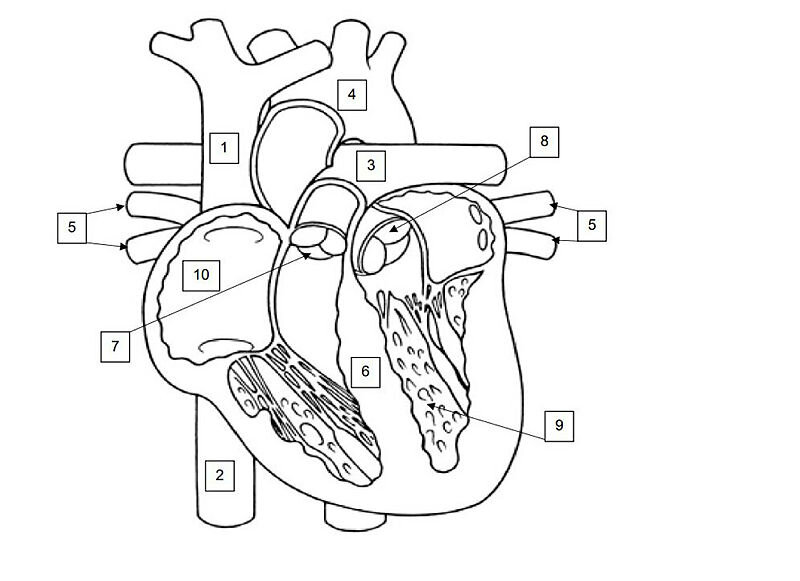

Navngi de ti nummererte strukturene på illustrasjonen av hjertet. Du kan velge å bruke norske og/eller latinske benevnelser. Svarene skrives i nummerert listeform på innleveringspapir. (5 poeng)

Sensorveiledning:

1. Øvre hulvene / v. cava superior

2. Nedre hulvene / v. cava inferior

3. Pulmonalarterie / lungearterie / a. pulmonalis

4. Hovedpulsåren / aorta

5. Lungevener / pulmonalvener / vv. pulmonales

6. Hjerteskilleveggen / septum

7. Pulmonalklaffen

8. Aortaklaffen

9. Venstre hjertekammer / venstre ventrikkel

10. Høyre forkammer / høyre atrium

Ved sensur gis 0,5 poeng for hvert riktig navn. Merk at det for noen av pilene kan være alternative benevnelser som godtas som riktig svar. Eksempelvis kan truncus pulmonalis være svaralternativ på punkt 3.

På punkt 9 kan endokard eller myokard være alternativer.